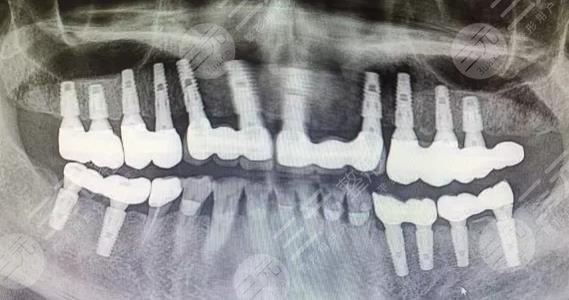

于是我就会这个方式,大概在爷爷咬完牙槽模型之后,一星期来做的口腔种植手术,刚开始爷爷还是很紧张,一直握着我的手不放开,但是舒适感体验果然是舒适,爷爷不一会儿就睡着了,对于种植牙过程,他除了基本没有什么不舒服的感觉,种植完之后。他总觉得自己的一口大白牙不舒服,可能是没有牙齿,习惯了,回家之后爷爷可以吃很多好东西了,牙齿也很洁白,露出了久违的笑容。